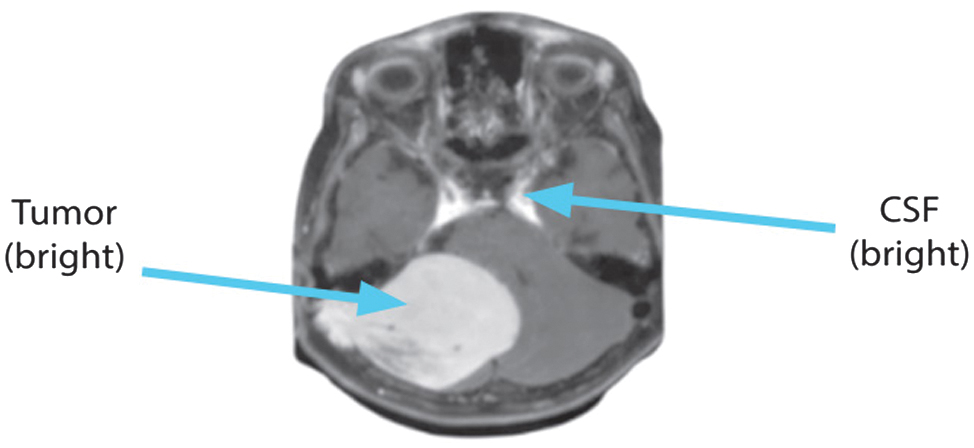

The CSF seems particularly bright because the T2-weighted sequences produce extended TE and TR durations. Fluids, bones, and air all seem black in the T2 sequence. Enhanced fluid content, which makes lesions look brilliant, is a hallmark of the inflammatory phase in the majority of illnesses. Fig. 3 shows the T2 picture in a sagittal view.